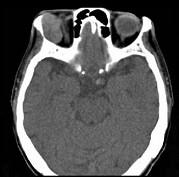

问题 男性,41岁,右侧眶外上方肿胀,可触及无痛性包块,CT及MRI检查如图所示,请选择最可能诊断()

选项 A.眶内血管瘤 B.眶内结核 C.眶内炎性假瘤 D.泪腺混合瘤 E.眶内囊肿

答案 D